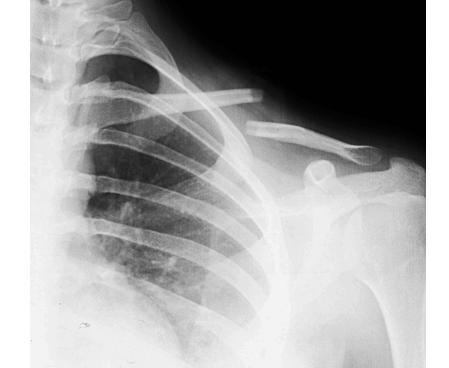

老李管不了电动车,赶紧打的就进来了医院急诊检查,结果片子一排,发现左边的锁骨从中间摔断了,而且骨头还错位了。老李左边锁骨中间鼓起来的那个“包”,其实并不是长了什么东西,而是断裂的骨折错位了,断开的骨头茬子从里面向外把皮给顶起来了。

锁骨骨折在生活中其实还是比较常见的,一般都是摔倒肩膀着地引起的,而且多见于儿童和年轻人。而且,锁骨骨折有个特点,那就是骨折最容易发生在中段,就像文章开头老李那样。

当外伤导致锁骨骨折时,会有锁骨区明显的疼痛感,而且这种疼痛感会随着活动患侧的胳膊而加重。如果骨折比较严重,或者移位明显,锁骨区还会有明显的肿胀、瘀斑和皮肤隆起。还有可可怕的,是骨折断端直接把皮肤顶破,骨头露出来......

而锁骨中段骨折又有它自己特殊的地方。因为锁骨的上面有颈部肌肉向上牵拉,锁骨下面有胸部肌肉向下牵拉,所以一旦锁骨中段发生骨折,颈部的肌肉向上拉骨折块,胸部的肌肉向下拉骨折块,就会出现像下图一样典型的骨折移位。